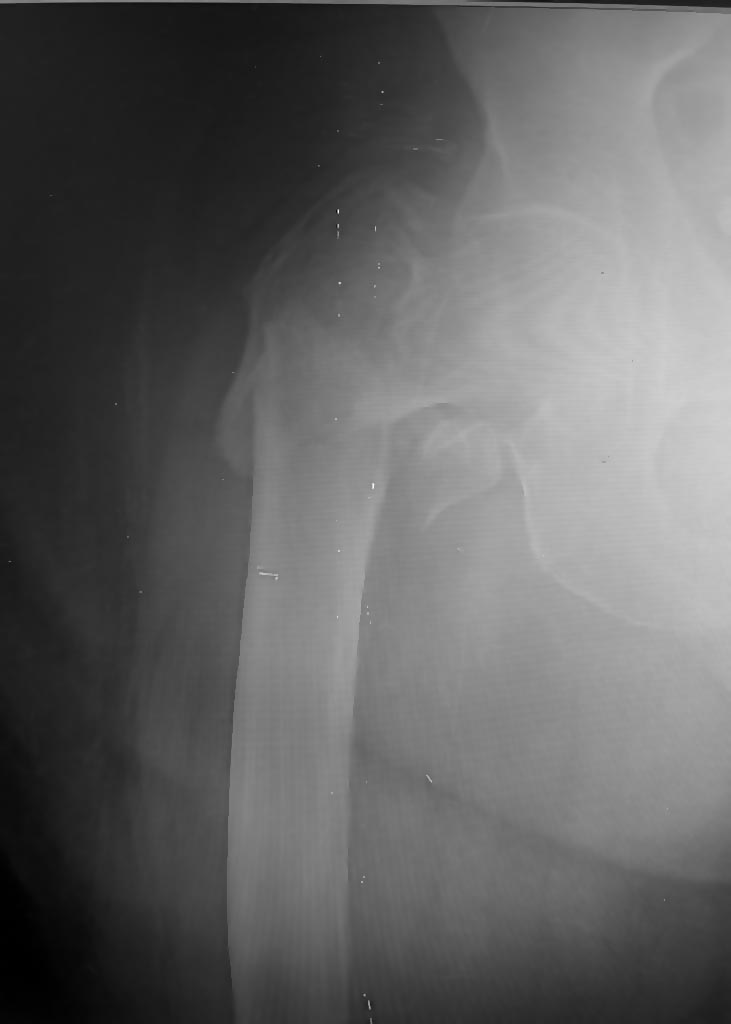

Какой репозиционный прием здесь лучше применить перед интрамедуллярным

штифтом? Второй проекции нет. Больная, 87 лет. Допольнительно:

вколоченный перелом шейки правой плечевой кости, консервативное лечение.